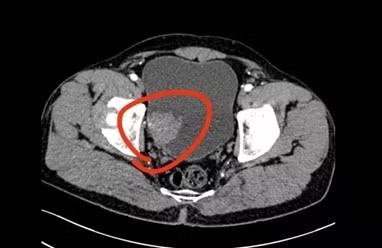

泌尿外科团队对康爷的病情和健康状况,进行了全面细致的分析,他被诊断为“高级别肌层浸润性膀胱癌”。

为了给康爷提供详尽的治疗方案,南山医院泌尿外科学科带头人张立元主任召集了全院多学科病例讨论。经讨论,多学科团队明确了手术指征,并制定了完善的治疗方案,即“腹腔镜下膀胱根治性切除术+Mainz II乙状结肠直肠膀胱术”。

6月17日,凭借丰富的临床经验和精湛的手术技艺,张立元主任带领团队利用先进的腹腔镜微创技术,仅通过腹部的四个微小切口,顺利游离并切除患者的膀胱、前列腺和精囊等,并将双侧盆腔淋巴结一并清扫干净。

随后,为了保障患者术后的生活质量,免于尿袋的痛苦,张立元主任利用康爷自身的乙状结肠和直肠,以去管化方式巧妙缝合,构建了一个低压力、大容量的“新膀胱”,最后将两侧的输尿管与“新膀胱”吻合,完成了尿流改道。